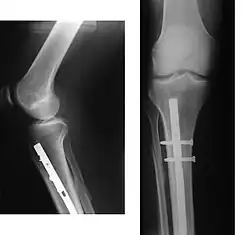

- Periprosthetic fracture – a fracture at the point of mechanical weakness at the end of an implant.

When the initial post-fracture oedema or swelling goes down, the fracture may be placed in a removable brace or orthosis. If being treated with surgery, surgical nails, screws, plates, and wires are used to hold the fractured bone together more directly. Alternatively, fractured bones may be treated by the Ilizarov method, which is a form of an external fixator.

Surgery

Surgical methods of treating fractures have their own risks and benefits, but usually, surgery is performed only if conservative treatment has failed, is very likely to fail, or is likely to result in a poor functional outcome.[42] With some fractures such as hip fractures (usually caused by osteoporosis), surgery is offered routinely because non-operative treatment results in prolonged immobilisation, which commonly results in complications including chest infections, pressure sores, deconditioning, deep vein thrombosis (DVT), and pulmonary embolism, which are more dangerous than surgery.[43] When a joint surface is damaged by a fracture, surgery is also commonly recommended to make an accurate anatomical reduction and restore the smoothness of the joint.